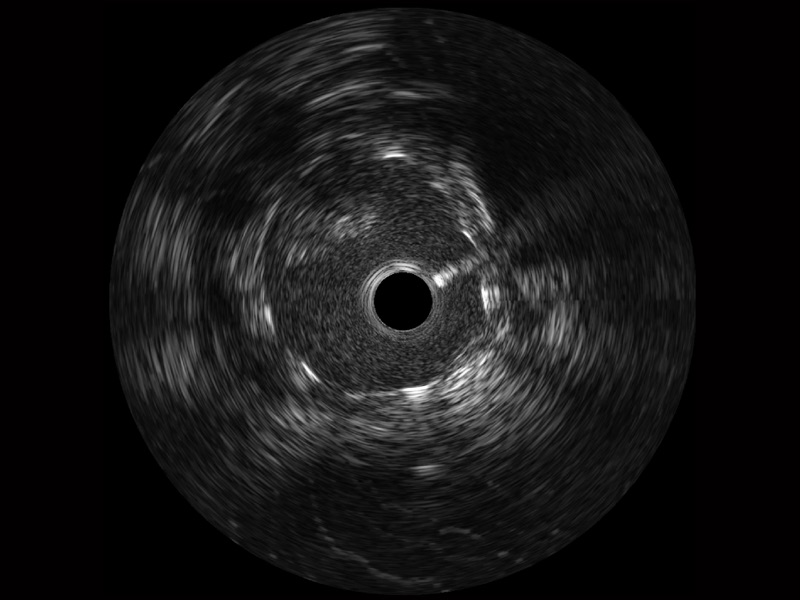

MILE米乐集团官网宽频IVUS图像

传统IVUS图像

对比传统IVUS导管成像,MILE米乐集团官网宽频IVUS图像的近场支架梁显影更细腻,远场中膜外血管仍清晰可辨,兼顾远中近,兼顾分辨力与穿透深度